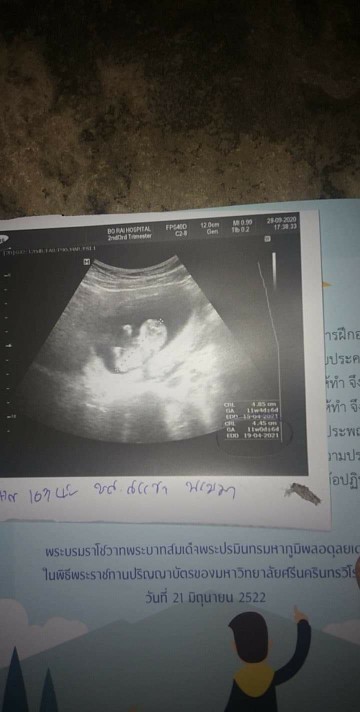

12สัปดาห์ เห็นชัดแล้วค่ะ

บ้านนี้ 13wคะ เป็นตัวแล้ว